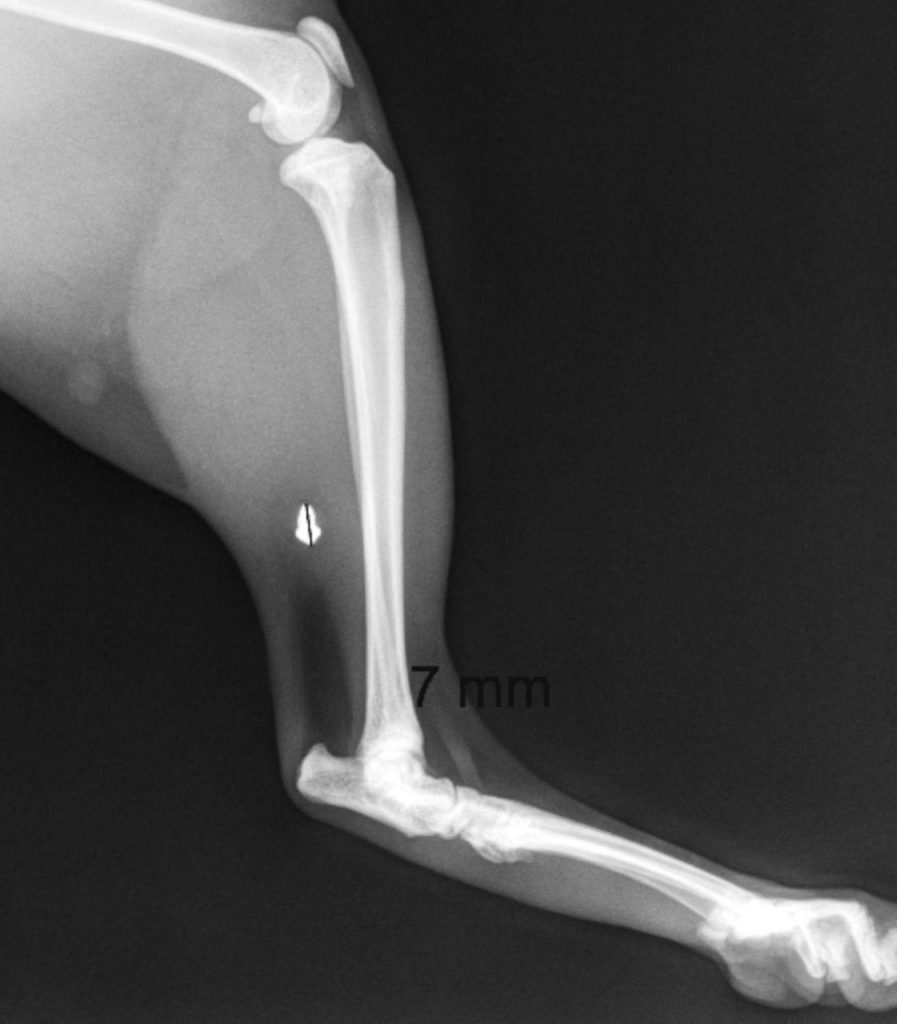

A l'aide d'une radiographie ayant mis en évidence la présence de plomb dans le muscle de sa cuisse, Vanessa a pu constater que son chat s'était bel et bien fait tirer dessus. Il a immédiatement été envoyé en salle d'opération.

Le lendemain, il m’a dit que la blessure était assez grave. Le plomb est entré par le haut de la cuisse et s’est logé dans le muscle. Il a dû recoudre la plaie, et ouvrir plus bas pour accéder au projectile et le retirer.